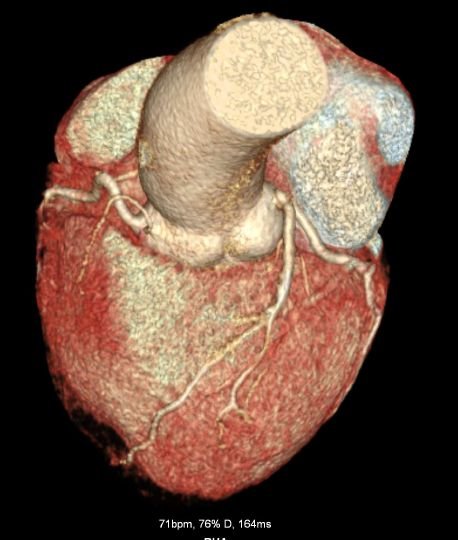

CT Cardiac Anatomy

CT Heart